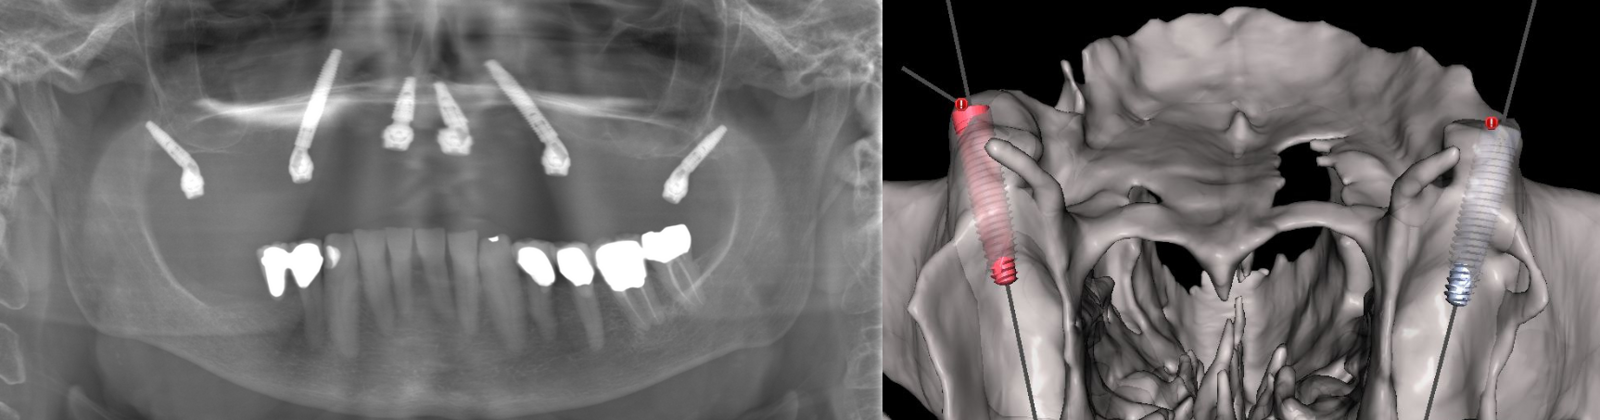

2. Diagnostiek en digitale behandelplanning

Gezien het extreem beperkte botvolume werd gekozen voor een vaste maxillaire rehabilitatie met een zygomatisch implantaatconcept, waarbij augmentatieve reconstructies werden vermeden. Met behulp van digitale planning in JDreal-software werden twee zygoma-implantaten en twee nasale/anterior-implantaten virtueel gepositioneerd (figuur 12). Op basis van deze planning werd een 3D metaal geprinte boormal ontworpen om een nauwkeurige, begeleide plaatsing volgens het geplande traject te kunnen garanderen.

Digitale planning van de implantaten (twee zygoma’s en twee nasale).

3. Chirurgische uitvoering

De chirurgie werd uitgevoerd onder lokale verdoving. Na een mid-crestale incisie werd een volledige flap opgeklapt met expositie van het zygoma. De 3D metaal geprinte boormal werd gefixeerd, waarna de implantaatkanalen werden voorbereid met een diamantboor. Vervolgens werden twee zygoma-implantaten (JD 3,9 × 37 mm) en twee nasale/anterior-implantaten (3,3 × 13 mm) geplaatst conform de digitale planning. Er werd een hoge primaire stabiliteit bereikt (>60 Ncm), waardoor directe belasting mogelijk was. In de onderkaak waren twee tissue level Straumann-implantaten geplaatst (figuur 13-15).

Postoperatieve CBCT-scan.

Chirurgische plaatsen van de implantaten.

Postoperatieve OPT.